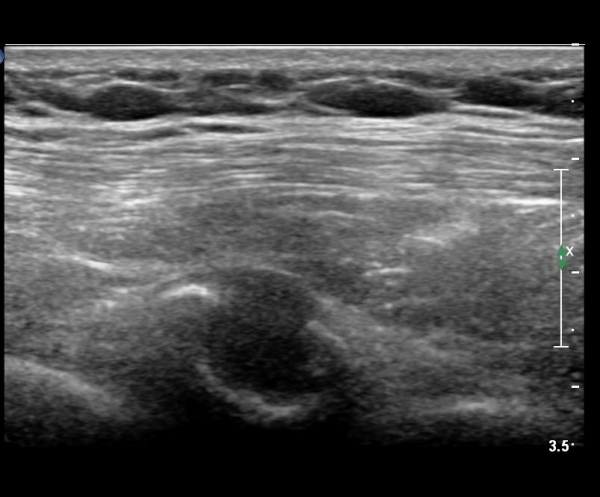

lin longitudinal scan of 7th. rib, appearance of bony mass(protrusion) just like callus(image 1).

on moving of prove a little, there is bony protrusion(osteoblastic lesion) and hypoechoic(osteolytic)  lesion(image 2, 3, 4).

in transverse scan, visualization of osteoblastic mass with central osteolytic lesion(image 5, 6).

As like this case, visualization of osteoblastic lesion and osteolytic lesion in simultaneously  suggests a malignant mass.